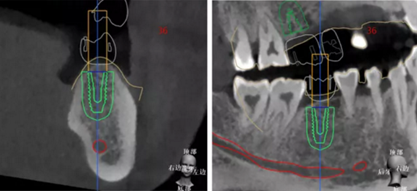

繪制下頜神經管

植體植入設計

設計植入5顆種植體

查看種植體螺絲通道穿出虛擬修復體的位置。

查看種植體在牙槽嵴頂穿出位置。

種植規(guī)劃與術后CBCT影像對比